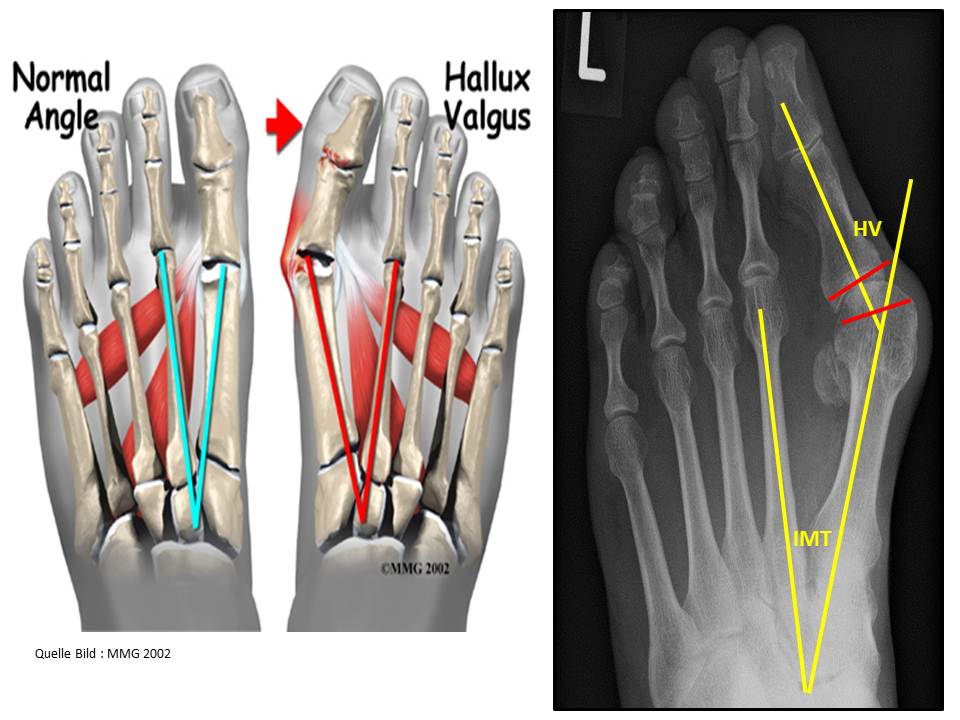

Beim Hallux valgus weicht am Vorfuß der erste Mittelfußknochen nach innen aus, was durch die Abflachung des Quergewölbes hervorgerufen wird. Dies führt zu einer Verschiebung der Großzehensehnen. Durch wiederum ändert sich die Zugrichtung der Großzehensehnen, wodurch die Großzehe nach außen gezogen wird. Hier entsteht das bekannte Überbein oder der Ballen unterhalb der Großzehe.

Bei der Beurteilung der Schwere des Hallux valgus wird der Winkel der Fehlstellung zwischen dem ersten und zweiten Mittelfußknochen (Intermetatarsal Winkel normal bis ca. 10°) und der entstandene Ballenwinkel (Halluxwinkel normal bis ca. 15°) gemessen. Die Röntgenaufnahme des Fußes muss unter Belastung erfolgen.

Leichte Hallux valgus:

Intermetatarsalgelenk-Winkel (IMT)<15° und Hallux valgus Winkel (HV)<28°

Mittelschwere Form des Hallux valgus:

Intermetatarsal-Winkel(ITM)>15° und Hallux Valgus Winkel(HV)<40°

Schwere Form des Hallux valgus:

Intermetatarsal-Winkel(ITM)>20° und Hallux valgus Winkel>40°